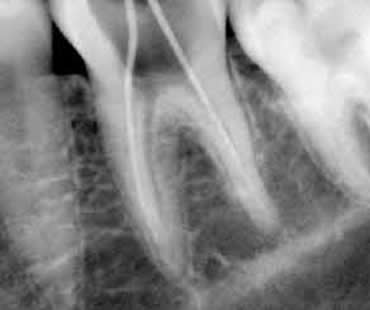

This is a common misconception. The pain associated with a root canal is caused by swelling and pressure from infection or trauma. During the procedure, your dentist removes the damaged pulp (the soft nerve center of the tooth), disinfects the area, and seals it to prevent further infection. Most patients experience only mild soreness afterward, and many report feeling immediate relief.

Pain is a common indicator of a problem, but not always. If the tooth root dies, you may not experience any symptoms. Dentists use diagnostic tools like temperature testing and percussion testing to assess the health of a tooth.